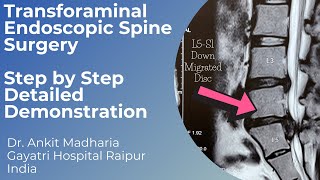

Percutaneous Transforaminal Endoscopic Lumbar Discectomy - Dr Manoj Sharma Transforaminal Endoscopic Discectomy | L5 S1 Down Migrated Disc | Dr Ankit Madharia | Detailed Video

Transforaminal Endoscopic Discectomy | L5 S1 Down Migrated Disc | Dr Ankit Madharia | Detailed Video Ep: 13 Still Confused About Slipped Disc Surgery? Watch This First! | Dr. SK Rajan

Percutaneous Transforaminal Endoscopic Lumbar Discectomy - Dr Manoj Sharma Transforaminal Endoscopic Discectomy | L5 S1 Down Migrated Disc | Dr Ankit Madharia | Detailed Video

Transforaminal Endoscopic Discectomy | L5 S1 Down Migrated Disc | Dr Ankit Madharia | Detailed Video Ep: 13 Still Confused About Slipped Disc Surgery? Watch This First! | Dr. SK Rajan